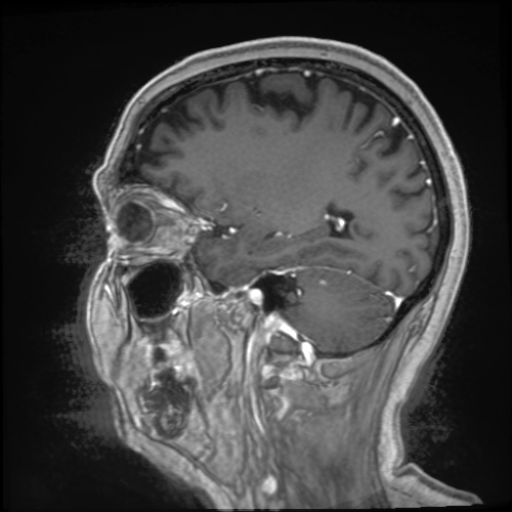

Refer to caption

Figure 2: Illustration of the preprocessing steps for extracting the initial low-dose subtraction image 𝐳~LDsubscript~𝐳LD\tilde{\mathbf{z}}_{\mathrm{LD}}over~ start_ARG bold_z end_ARG start_POSTSUBSCRIPT roman_LD end_POSTSUBSCRIPT from the pre-contrast 𝐱PCsubscript𝐱PC\mathbf{x}_{\mathrm{PC}}bold_x start_POSTSUBSCRIPT roman_PC end_POSTSUBSCRIPT and low-dose 𝐱LDsubscript𝐱LD\mathbf{x}_{\mathrm{LD}}bold_x start_POSTSUBSCRIPT roman_LD end_POSTSUBSCRIPT image. The top images in the steps show the transformed low-dose image while the bottom images visualize the effects on the subtraction image.

To compute the subtraction images 𝐳{LD,SD}subscript𝐳LDSD\mathbf{z}_{\{\mathrm{LD},\mathrm{SD}\}}bold_z start_POSTSUBSCRIPT { roman_LD , roman_SD } end_POSTSUBSCRIPT from a pre-contrast 𝐱PCsubscript𝐱PC\mathbf{x}_{\mathrm{PC}}bold_x start_POSTSUBSCRIPT roman_PC end_POSTSUBSCRIPT and CE 𝐱{LD,SD}subscript𝐱LDSD\mathbf{x}_{\{\mathrm{LD},\mathrm{SD}\}}bold_x start_POSTSUBSCRIPT { roman_LD , roman_SD } end_POSTSUBSCRIPT image pair, we perform the preprocessing pipeline illustrated in Figure 2. First, the brain region 𝐛{0,1}n𝐛superscript01𝑛\mathbf{b}\in\{0,1\}^{n}bold_b ∈ { 0 , 1 } start_POSTSUPERSCRIPT italic_n end_POSTSUPERSCRIPT is extracted by an affine registration of an atlas brain towards the pre-contrast image 𝐱PCsubscript𝐱PC\mathbf{x}_{\mathrm{PC}}bold_x start_POSTSUBSCRIPT roman_PC end_POSTSUBSCRIPT to minimize the effects of motion artifacts from facial regions in the subsequent steps. Second, the itk-elastix library is used to co-register the low-dose 𝐱LDsubscript𝐱LD\mathbf{x}_{\mathrm{LD}}bold_x start_POSTSUBSCRIPT roman_LD end_POSTSUBSCRIPT or standard-dose 𝐱SDsubscript𝐱SD\mathbf{x}_{\mathrm{SD}}bold_x start_POSTSUBSCRIPT roman_SD end_POSTSUBSCRIPT images to the corresponding pre-contrast images. Third, each scan is coarsely normalized by mapping its 95%percent9595\%95 % intensity percentile of the brain region to 1111. This coarse alignment of the intensity values is refined by a radiometric registration step computing a scalar to minimize a robust distance as performed in [9].

Let us denote these initial subtraction images by 𝐳~{LD,SD}subscript~𝐳LDSD\tilde{\mathbf{z}}_{\{\mathrm{LD},\mathrm{SD}\}}over~ start_ARG bold_z end_ARG start_POSTSUBSCRIPT { roman_LD , roman_SD } end_POSTSUBSCRIPT. We further processed them to normalize the noise level within the images, which is often spatially varying in parallel imaging [31]. Since the contrast signal is positive in the subtraction images, we use the negative values in the brain region to roughly estimate the noise levels σLD,σSDsubscript𝜎LDsubscript𝜎SD\sigma_{\mathrm{LD}},\sigma_{\mathrm{SD}}italic_σ start_POSTSUBSCRIPT roman_LD end_POSTSUBSCRIPT , italic_σ start_POSTSUBSCRIPT roman_SD end_POSTSUBSCRIPT of the low-dose and standard-dose subtraction image, respectively. Then, we mask out potential contrast-enhancing pixels and artifacts by removing pixels that are outside of ±2σ{LD,SD}plus-or-minus2subscript𝜎LDSD\pm 2\sigma_{\{\mathrm{LD},\mathrm{SD}\}}± 2 italic_σ start_POSTSUBSCRIPT { roman_LD , roman_SD } end_POSTSUBSCRIPT. On this masked subtraction image, we estimate the local mean 𝐦{LD,SD}nsubscript𝐦LDSDsuperscript𝑛\mathbf{m}_{\{\mathrm{LD},\mathrm{SD}\}}\in\mathbb{R}^{n}bold_m start_POSTSUBSCRIPT { roman_LD , roman_SD } end_POSTSUBSCRIPT ∈ blackboard_R start_POSTSUPERSCRIPT italic_n end_POSTSUPERSCRIPT and standard deviation 𝐬{LD,SD}nsubscript𝐬LDSDsuperscript𝑛\mathbf{s}_{\{\mathrm{LD},\mathrm{SD}\}}\in\mathbb{R}^{n}bold_s start_POSTSUBSCRIPT { roman_LD , roman_SD } end_POSTSUBSCRIPT ∈ blackboard_R start_POSTSUPERSCRIPT italic_n end_POSTSUPERSCRIPT using large Gaussian filter kernels with a standard deviation of 16161616 pixels. These local noise characteristics are then used to correct field-inhomogeneities and normalize the noise level within the subtraction images, such that